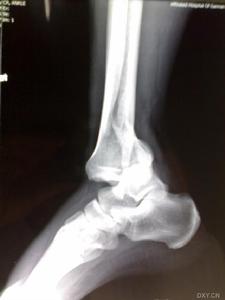

跟骨骨折影像病人有典型的外傷史,患足承重困難和足跟疼痛,局部觸痛、腫脹和皮下淤血斑亦多明顯。在較嚴重的壓縮骨折時,除可見到足後跟的高度變低和足跟橫徑變寬以及外踝下部正常凹陷消失外,距下關節話動亦完全喪失。但跟骨周邊骨折僅有局部腫脹及壓痛,而距下關節活動範圍多屬正常。x線正、側、軸位片可明確跟骨的結節關節角和其橫徑寬度的改變。

影像學表現

(1)跟骨前突骨折。

(2)跟骨結節的垂直骨折。

(3)載距突骨折。

(4)跟骨壓縮性骨折。

(5)跟骨粉碎性骨折。